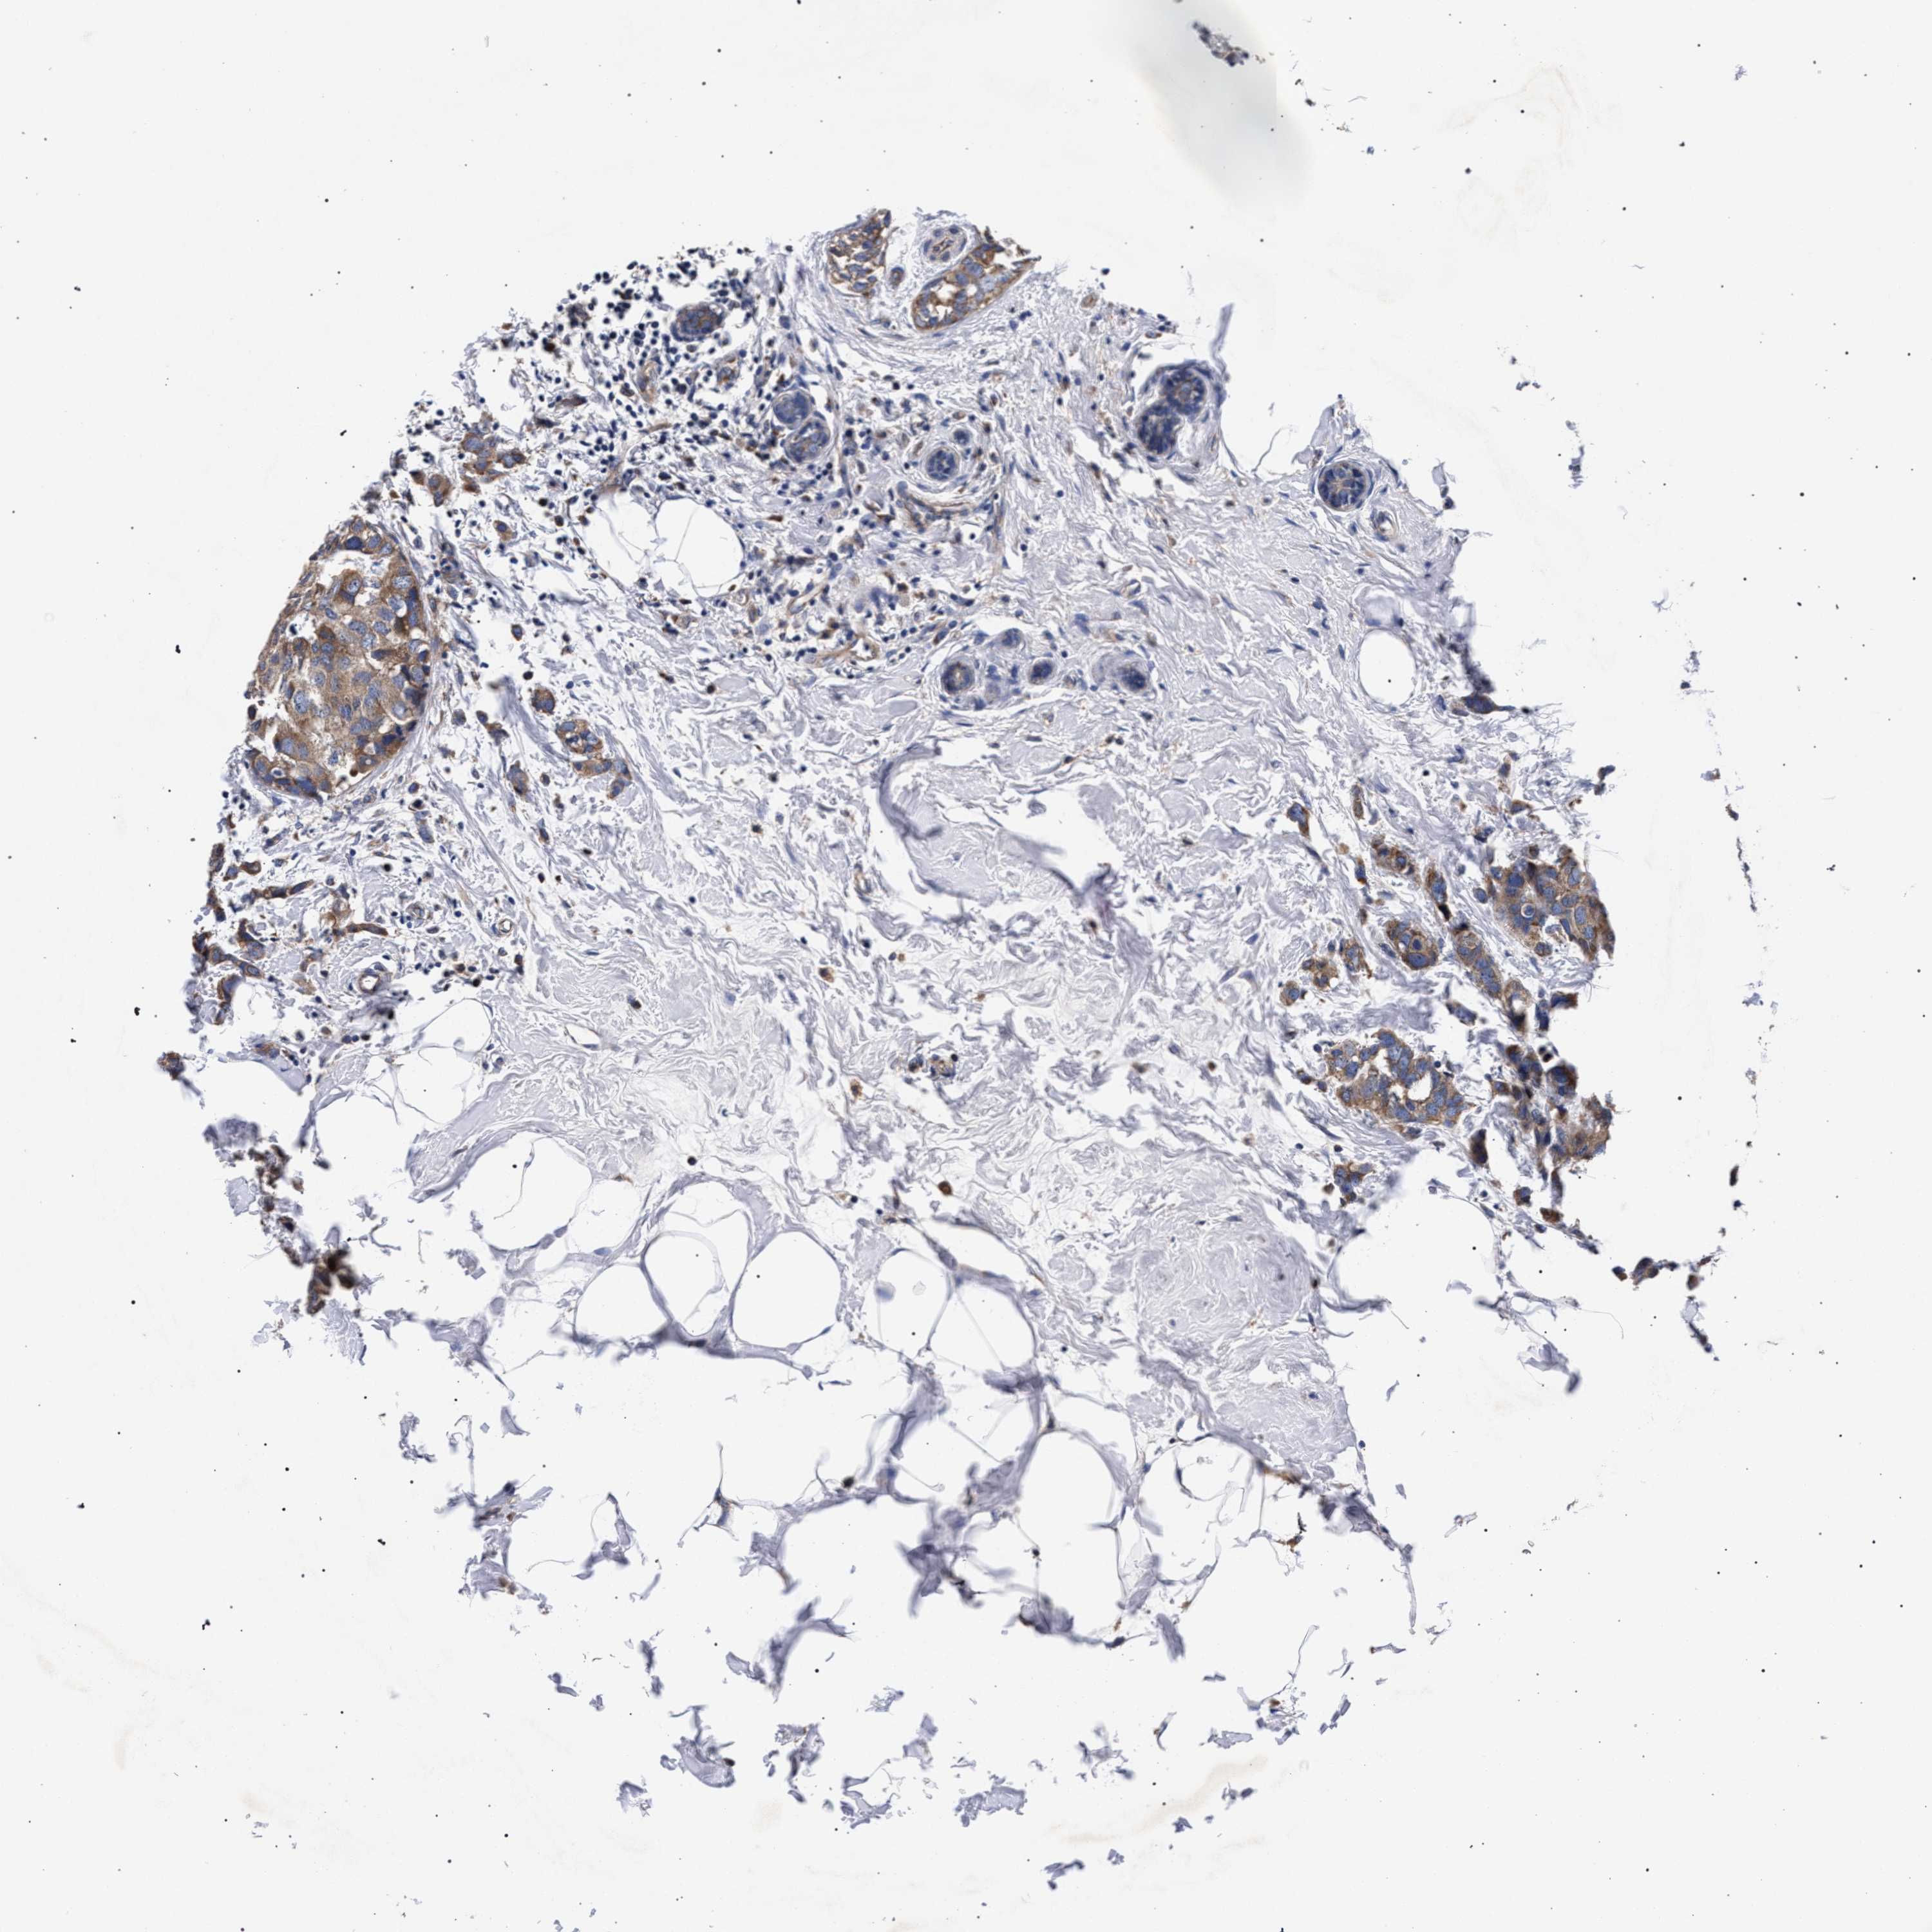

CANCER BREAST CANCER Show tissue menu

BRCA TCGA BRCA VALIDATION PROTEIN EXPRESSION

Breast cancer

Human cancer